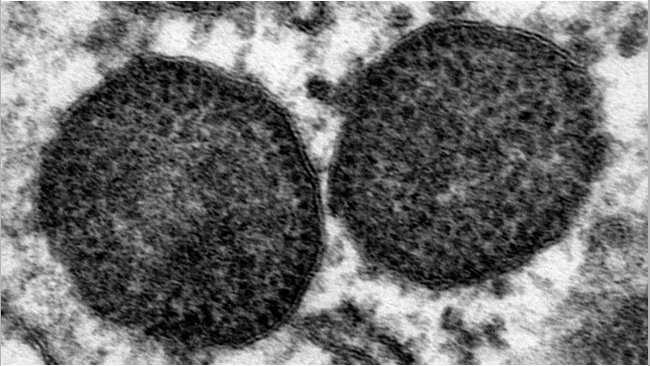

El circovirus porcino 2 (PCV-2) es una de las infecciones virales más frecuentes en cerdos, causando un impacto económico notable debido a los costos directos e indirectos de su control. Como otros virus ssDNA, el PCV-2 se caracteriza por una alta tasa de evolución, lo que lleva a la aparición de una gran cantidad de variantes con diferentes características biológicas y epidemiológicas. Con el tiempo, se han hecho varios intentos para organizar la heterogeneidad genética del PCV-2 en genotipos reconocidos. Esta categorización ha simplificado claramente las investigaciones epidemiológicas, permitiendo identificar diferentes patrones espaciales y temporales entre los genotipos. Además, también se ha planteado la hipótesis de la virulencia variable y la efectividad de la vacuna. Sin embargo, el rápido aumento en la actividad de secuenciación, junto con la alta variabilidad viral per se, ha desafiado la nomenclatura establecida previamente, conllevando a la definición de varios genotipos específicos de estudios e obstaculizando la capacidad de realizar estudios epidemiológicos comparables.

Sobre la base de estas premisas, se presenta un esquema de clasificación actualizado. Reconociendo la imposibilidad de definir un límite claro de distancia entre dos secuencias (p-distance) entre los clusters, el presente estudio propone una definición de genotipo basada en la filogenia en base a tres criterios: una p-distance intra-genotipo máxima del 13% (calculada sobre el gen ORF2), valores de bootstrap en el nodo interno correspondiente superior al 70% y al menos 15 secuencias disponibles. Este esquema permitió definir 8 genotipos (PCV-2a a PCV-2h), seis de los cuales se habían propuesto previamente. Para minimizar el inconveniente de implementar una nueva clasificación, los nombres más comunes se han mantenido en lo posible. El análisis de metadatos asociados a secuencias destacó una actividad de secuenciación altamente desequilibrada en términos de distribución geográfica, temporal y de huésped. El escenario de epidemiología molecular del PCV-2 aparece por lo tanto caracterizado por un sesgo grave que podría conducir a asociaciones falsas entre las características genéticas y las características virales epidemiológicas/biológicas. Si bien la clasificación recomendada puede establecer un "lenguaje común" para futuros estudios, se deben hacer más esfuerzos para lograr una representación más homogénea e informativa del escenario global del PCV-2.